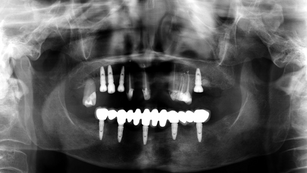

Treatment of peri-implantitis by mechanical cleansing using I-brush II & T-brush

Situation Peri-implantitis were found around implants #46,47&48. Pre-operative Panorama Clinical buccal view of implants #46,47&48....